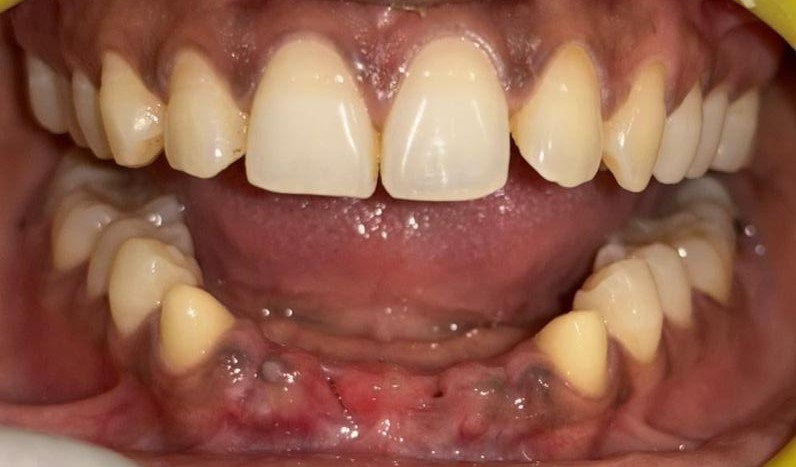

After After

Before Before